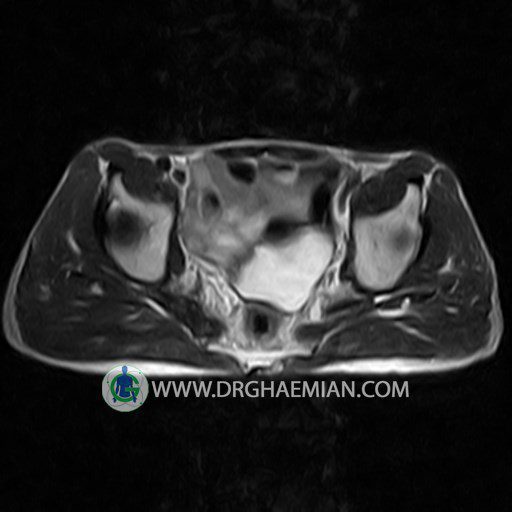

پزشکان اغلب از تصویربرداری ام آر آی برای تشخیص و درمان عارضه های پزشکی که فقط با استفاده از اشعه ایکس یا میدان مغناطیسی و امواج رادیویی قابل مشاهده است، استفاده می کنند. دستگاه ام آر آی تصاویر دقیق از ساختار های داخلی بدن ایجاد می کند. در این کیس استئومیلیت لگن، آتروز و سنیویت دیده می شود.

HIP JOINT MRI

( without contrast )

Technique : coronal STIR , coronal T2 , Axial T1 , axial T2 .

– Heterogeneous signal change (high T2/STIR , low T1) in proximal metaepiphysis of left femur without articular surface irregularity suggestive for bone bruise (stress fracture?), osteomyelitis & arthritis and marrow infiltration (less probable)

– Left hip joint effusion suggestive for synovitis

are seen.

COMMENT: Clinical correlation and MRI with contrast are recommended.